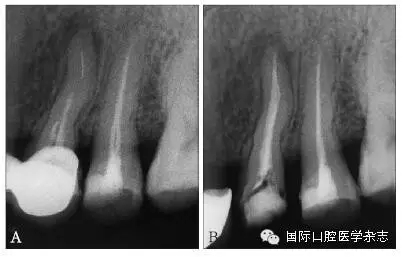

3.2.1 牙本質(zhì)厚度評(píng)估 取出分離器械需要損失部分牙本質(zhì),牙本質(zhì)的損失量包括縱向損失和橫向損失。縱向損失決定于取出時(shí)分離器械冠方末端需要暴露的長度,橫向損失決定于分離器械的斷端直徑以及選用取出器械的方法(如超聲法或是環(huán)鉆法等)。牙本質(zhì)損失量過多會(huì)導(dǎo)致根管穿孔、根管折斷等并發(fā)癥[7](圖3)。

A:紅色及綠色的部分分別表示用改良GG鉆及超聲工作尖去除牙本質(zhì)的量;B:MicroCT掃描圖像顯示取出下頜第一磨牙近頰根管中分離器械后,導(dǎo)致了根管穿孔。

圖 3 取分離器械過程中會(huì)導(dǎo)致牙本質(zhì)損失,甚至穿孔等并發(fā)癥

目前,對(duì)于分離器械周圍牙本質(zhì)厚度的評(píng)估以及取出后殘余牙本質(zhì)厚度的預(yù)測主要需借助影像學(xué)檢查,例如根尖片、錐形束CT(cone beamcomputed tomography,CBCT)圖像等。傳統(tǒng)的平行投照的根尖片無法反映三維立體結(jié)構(gòu),且往往存在解剖結(jié)構(gòu)影像的重疊,不利于臨床判斷,具有一定的局限性。多位學(xué)者[10]的研究表明:平行投照的根尖片會(huì)高估實(shí)際的牙本質(zhì)壁的厚度。一些學(xué)者[11-12]的研究表明:當(dāng)分離器械位于上頜第一磨牙近中根管時(shí),采用成角投照(21°)的拍攝技術(shù)與平行投照技術(shù)得到的X線片相比,能更準(zhǔn)確地評(píng)估牙本質(zhì)的厚度,為分離器械取出與否提供指導(dǎo)(圖4)。近年來,CBCT在牙髓病學(xué)中的應(yīng)用越來越廣泛,由于CBCT能清楚地反映牙及牙根周圍組織的三維立體結(jié)構(gòu),為牙本質(zhì)厚度的評(píng)估與預(yù)測提供了可行性(圖5);因此,CBCT在器械分離的病例術(shù)前風(fēng)險(xiǎn)評(píng)估方面具有較好的應(yīng)用前景。

A、B:采用平行投照技術(shù)獲得的圖像,模擬取出分離器械后殘余牙本質(zhì)的厚度,分離器械分別位于根管口下3 mm和5 mm;C、D:采用成角投照技術(shù)獲得的圖像,模擬取出分離器械后殘余牙本質(zhì)的厚度,分離器械分別位于根管口下3 mm和5 mm。

圖 4 平行投照與成角投照拍攝技術(shù)對(duì)牙本質(zhì)厚度的評(píng)估

圖 5 使用CBCT評(píng)估分離器械周圍牙本質(zhì)厚度